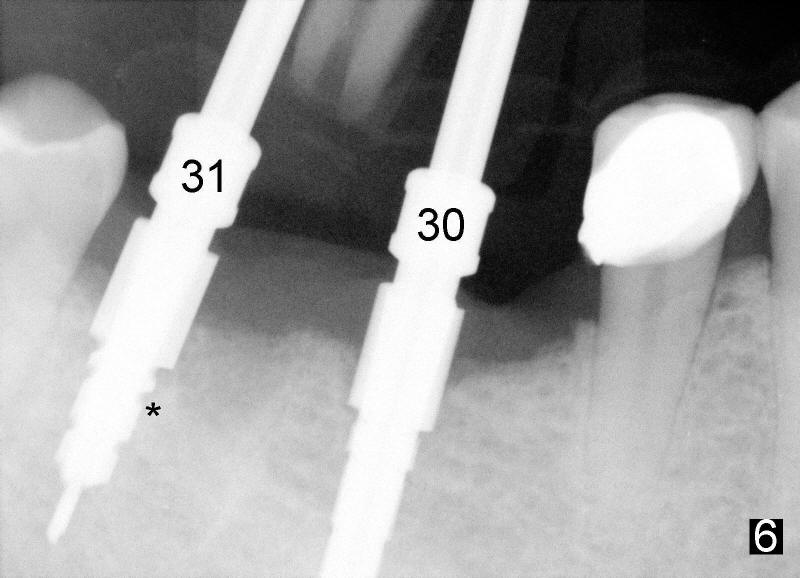

Six weeks post-extraction, a straight incision is made along the crest of #30/31. Without raising flap, #15 surgical blade, bone scalpels (4,5,6 mm wide) and bone blades (4,5.5,7.5 mm wide) ) (Fig.4 white line (illustration); Tatum Surgical) are used to expand the septum buccolingually (arrows). Then round tapered osteotomes (Fig.5 black circle (illustration)) are used to expand the septum circumferentially (arrows). Bone expansion with osteotomes alternates with sequential drills using irrigation. Fig.6 shows 4x17 and 4x14 mm drills placed in sockets #30 and 31, respectively. It appears that osteotomies are placed somewhat distally. The drill #31 is distal to the septum (*).